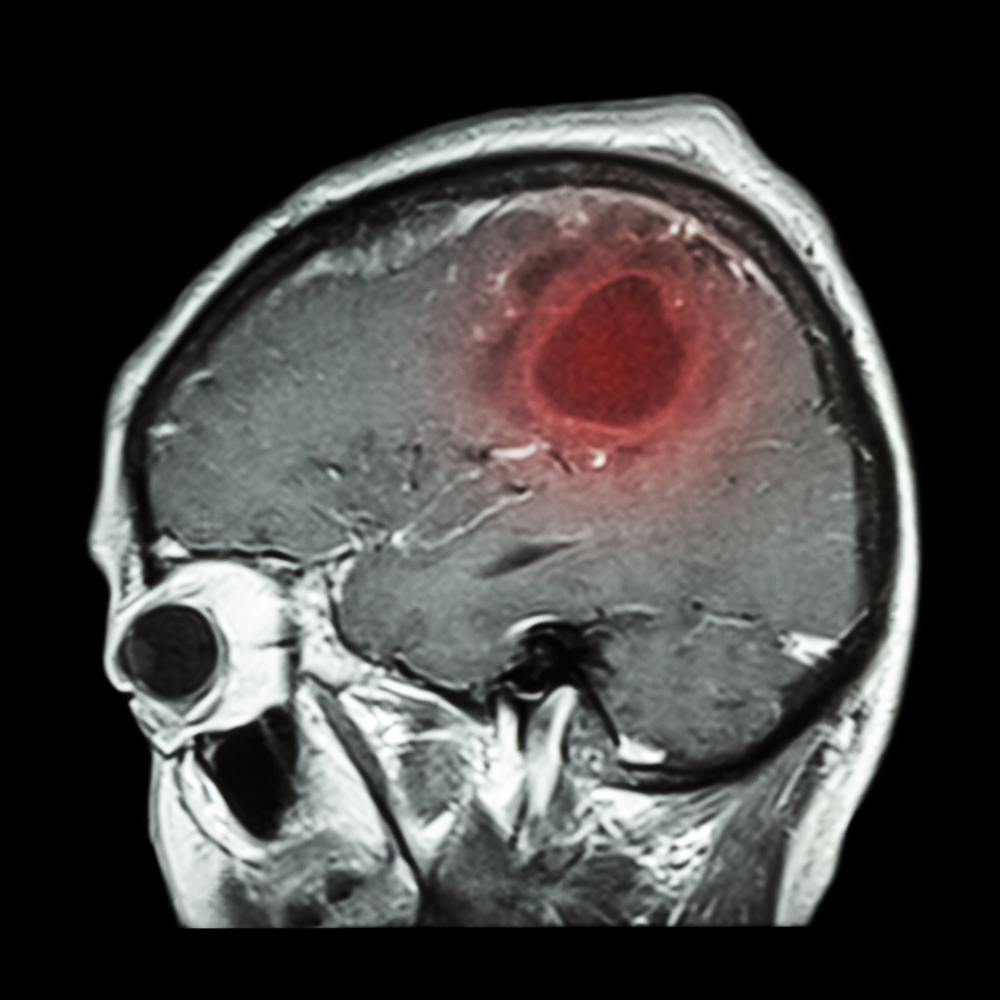

Опухоли головного мозга хоть и не являются лидерами среди всех онкологических процессов, тем не менее, представляют собой опасность для жизни человека. В этой статье мы поговорим о том, чем проявляет себя опухоль головного мозга, какие симптомы она вызывает.

Опухоль головного мозга – это любая опухоль, расположенная внутри черепа. Этот вид онкологического процесса составляет 1,5% от всех известных медицине опухолей. Встречаются в любом возрасте, независимо от пола. Опухоли головного мозга могут быть доброкачественными и злокачественными. Также их делят на:

По гистологическому типу насчитывается более 120 видов опухолей. Каждый тип имеет свои особенности не только строения, но и скорости развития, места расположения. Однако все опухоли головного мозга любого вида объединяет тот факт, что все они являются «плюс»-тканью внутри черепа, то есть растут в ограниченном пространстве, сдавливая рядом расположенные структуры. Именно этот факт и позволяет объединять симптомы различных опухолей в единую группу.